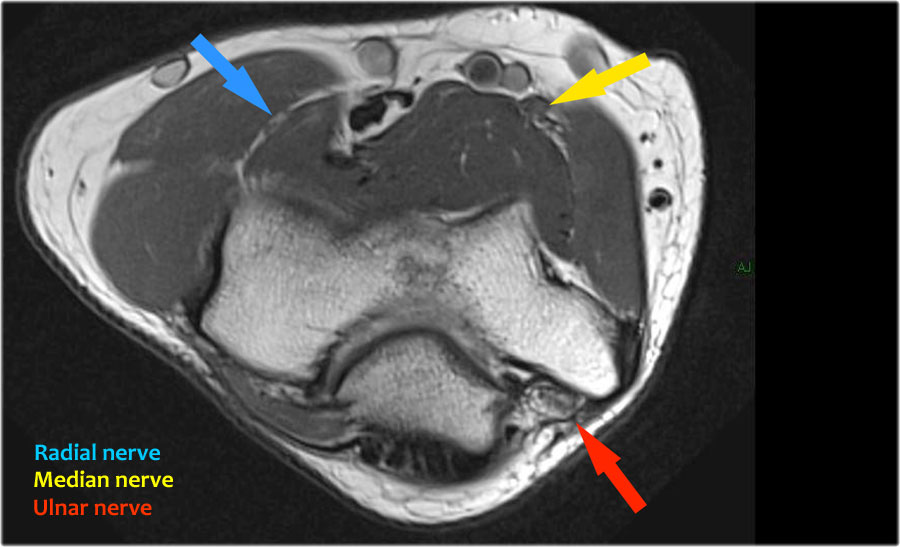

Scroll through the images.

Ulnar nerve

Ở đây chúng ta thấy dây thần kinh trụ nằm trong ống trụ.

Bó sau của dây chằng bên trụ tạo thành sàn của ống, trong khi mạc hãm tạo thành trần của ống.

Radial nerve

Dây thần kinh quay có thể được xác định rõ nhất ở mức chỏm xương quay, nơi có thể quan sát thấy các nhánh nông và nhánh sâu trong ống xương quay (mũi tên).

This is a very consistent place to find the radial nerve.